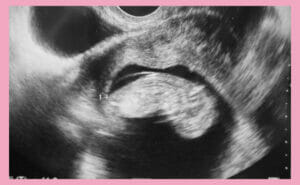

高齢出産で気を付けるべきこと:健康とリスク管理 2026.01.16 妊娠超初期 ダウン症(21トリソミー)不安全常染色体全領域部分欠失疾患全常染色体全領域部分重複疾患出生前診断妊娠後期妊娠期間妊娠検査 エコー妊婦健診気を付けること症状羊水検査遺伝子疾患高齢出産